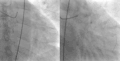

Angiograma coronario, con un vídeo a la izquierda que muestra una estenosis crítica (95%) de la LAD proximal en un paciente con síndrome de Wellens; El vídeo de la derecha muestra al mismo paciente después de la reperfusión . -